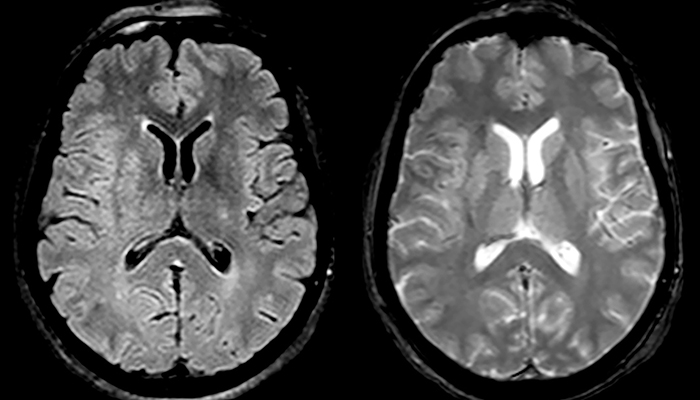

Multiple sclerosis imaging requires precision, speed

When multiple sclerosis (MS) is suspected, clinicians need a diagnosis early on, so treatment can begin as soon as possible. “A challenge for imaging is that MS lesions in the brain and spine may be very small,” says Dr. Savatovsky. “We need precise imaging to tell exactly where the lesion is, so we need high quality, very high resolution images, preferably in 3D[1]. We need to know if a high T2 signal intensity is suggestive of MS or just aspecific. And we want to visualize active lesions very well.”

“Ingenia 3.0T provides us very good image quality with high SNR, even if we push the resolution. For example, in FLAIR images we may have an isotropic resolution of 0.9 mm. Ingenia allows us to use 3D T1 TSE with BrainView, which has a better sensitivity than 2D spin echo imaging[2] and 3D gradient echo imaging. Ingenia also provides highly reproducible exams, which is important in MS imaging so that follow-up exams at different time points are done the same way.”